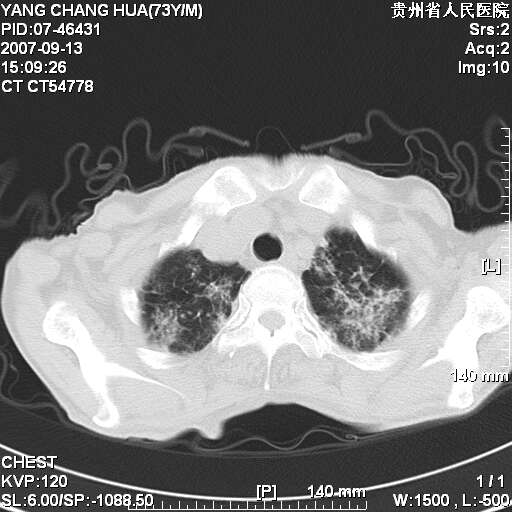

图像没有传全。肺部为感染性病灶;肺囊肿;双侧胸腔积液;肝脾肿大;腹水。

双肺部为感染性病灶.双侧胸腔积液;肝脾肿大;腹水.

双肺部为感染性病灶.双侧胸腔积液;肝脾肿大;脾脏密度不均,不除外脾侵润?腹水.

双肺部为感染性病灶.双侧胸腔积液;肝脾肿大;腹水

图片不全.就这几张图片.无法诊断淋巴瘤的,我考虑:双肺部为炎性病灶.双侧胸腔积液;肝脾肿大;腹水

双肺点片状影,以双上肺改变明显.双侧胸腔积液.为感染性病灶,但不除外结核.

双上肺继发型肺结核。

双侧胸腔积液。

双肺散在斑片状及多发小结节状阴影,边缘模糊,双上肺野明显,双侧胸膜腔少量积液,纵隔及肺门区未见明显肿大淋巴结,肝脾肿大,脾内见多发低密度区,结合临床考虑恶性淋巴瘤(肺内表现为肺炎肺泡型),单看影像表现,肺结核不能排除。建议结合实验室检查或表浅淋巴结活检。